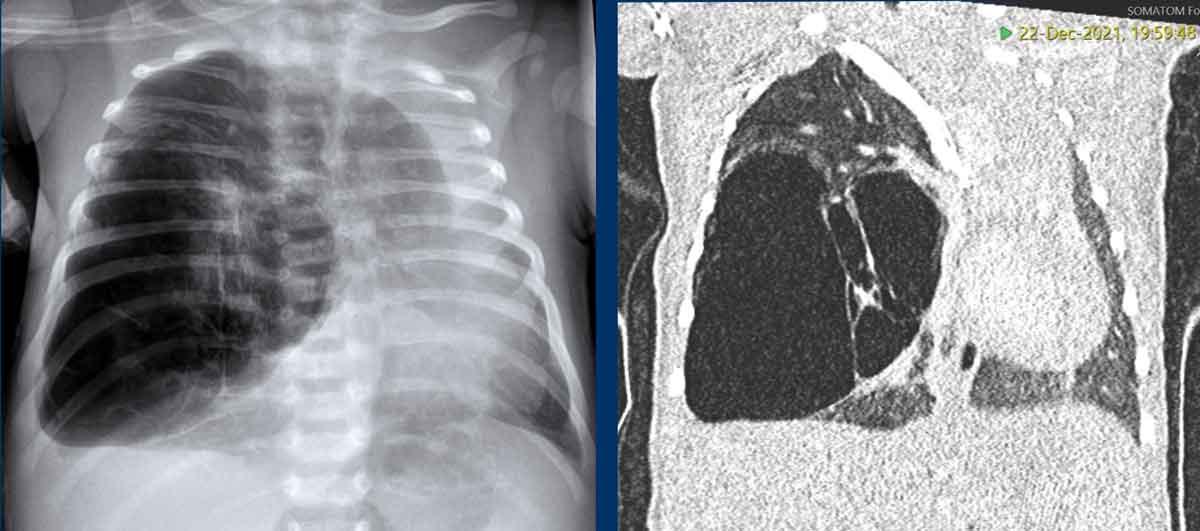

Hình ảnh của một trẻ sơ sinh đủ tháng với suy hô hấp nhẹ.

Trước sinh có nghi ngờ về CPAM.

Phim X-quang ngực và CT cho thấy ứ khí thùy trên phổi phải với biến dạng cấu trúc.

Thùy dưới phổi phải bị chèn ép, nhưng có thể có cấu trúc bình thường.

Trung thất và tim bị đẩy lệch, xẹp phổi trái.

Hình ảnh của một trẻ sơ sinh 6 tháng tuổi với các triệu chứng hô hấp nhẹ.

Phim X-quang cho thấy ứ khí quá mức ở thùy trên phổi trái với sự dịch chuyển của các cấu trúc đường giữa và xẹp phổi một phần ở thùy dưới.

The CT confirms overinflation

of the right upper lobe.